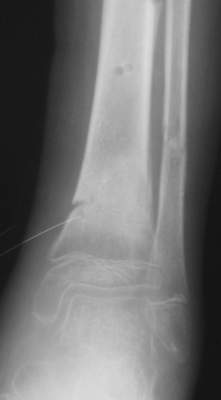

Это сросшийся перелом малоберцовой кости. И ложный сустав

н\3 б\берцовой кости.

Так как речь зашла непосредственно о травме, см этапные

снимки. Как все было

Первичные

Вытяжение

Фиксация

в гипсе

Промежуточный

A> Это сросшийся перелом малоберцовой кости. И ложный сустав

A> н\3 б\берцовой кости.

Таперича это ясно.